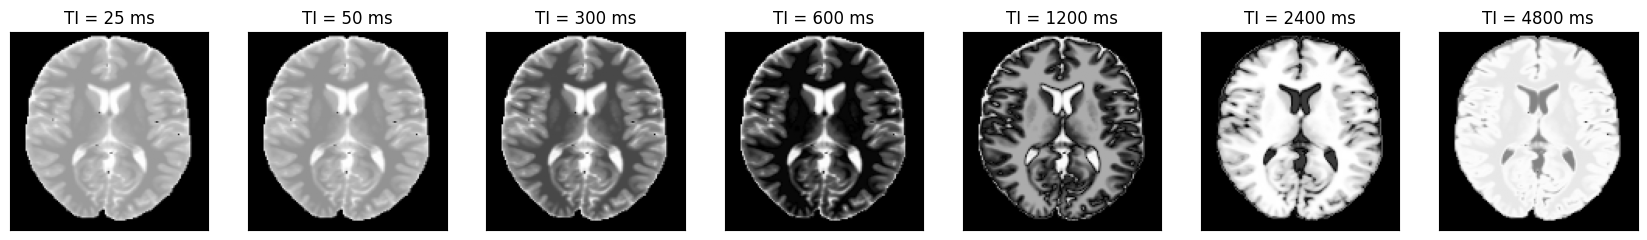

We can now plot the images at different inversion times.

idat = idata.data.abs().numpy().squeeze()

fig, ax = plt.subplots(1, idat.shape[0], figsize=(3 * idata.shape[0], 3))

for i in range(idat.shape[0]):

ax[i].imshow(idat[i, :, :], cmap='gray')

ax[i].set_title(f'TI = {int(idata.header.ti[i] * 1000)} ms')

ax[i].set_xticks([])

ax[i].set_yticks([])

_images/3634d900be83be0ad95b5a319d675697c0657ae7655f09b4cffa664d6344ff01.png